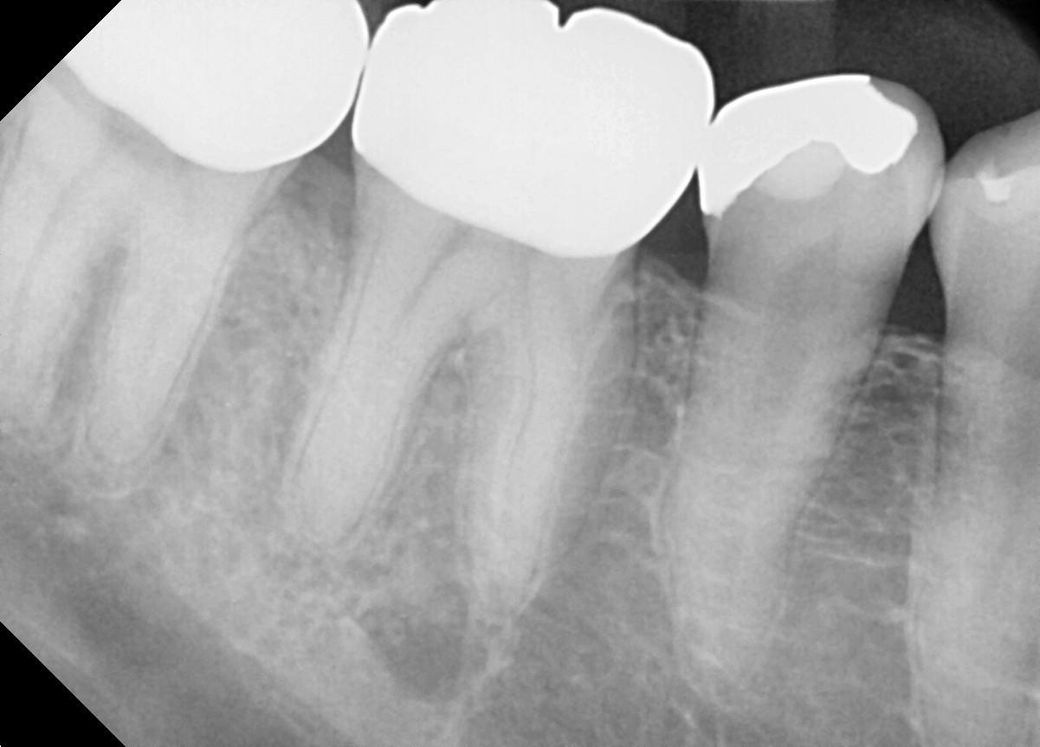

몇년전부터 오른쪽 아래에 반복적인 어금니 통증이 있었습니다. 그런데 어느 치아인지 정확하게 느낌이 오지 않았고 치과에서도 치아 자체에는 큰 문제는 없다 하셨습니다. 그런데 스케일링만 하면 통증이 사라졌었는데요, 최근에는 스케일링하고도 통증이 다시 돌아오는 주기가 점점 빨라지기 시작했습니다. 몇년전에는 스케일링을 한번 하면 3~6개월까지는 괜찮았는데, 지금은 스케일링 하고 나서 1~2개월 이후에 다시 아프기 시작합니다. 가까운 치과에서 씨티 촬영하니 오른쪽 아래 어금니에 뼈가 많이 녹아있다는걸 발견해 주셨는데요, 그게 원인인것 같다고 하시더라구요. 그부분에 하루에 한번씩 치간칫솔을(헥사메딘 묻혀서) 넣었다 뺏다해서 닦아주면서 관리해주라고 하십니다. 이게 적절한 방법인가요?

참고하실수 있도록 최근에 촬영한 문제가 되는 부위의 CT와 X레이사진 첨부합니다.

• 1번 째 사진

• 2번 째 사진

• 3번 째 사진